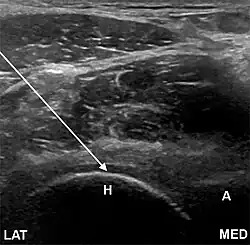

Anterolateral approach, here shown as a transverse image. The needle will rest on the femoral head (arrow). A, acetabulum; H, femoral head; N, femoral neck; LAT, lateral; MED, medial.[1]

• The anterolateral approach, with the ultrasound probe oriented axially and the femoral head and acetabular rim in view. This often shortens the distance from needle skin entry to joint compared to the longitudinal approach making it a useful approach in larger patients. The introduced needle remains lateral to the femoral neurovascular bundle, and the needle is advanced until its tip rests on the femoral head.